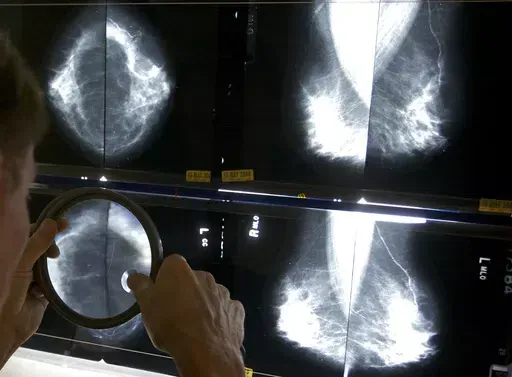

Regular mammograms to screen for breast cancer should start younger, at age 40, according to an influential U.S. task force. Women ages 40 to 74 should get screened every other year, the group said.

Previously, the task force had said women could choose to start breast cancer screening as young as 40, with a stronger recommendation that they get the exams every two years from age 50 through 74.

The announcement Tuesday from the U.S. Preventive Services Task Force makes official a draft recommendation announced last year. The recommendations were published in the Journal of the American Medical Association.

Age 40 is when mammograms should start for women, transgender men and nonbinary people at average risk. They should have the X-ray exam every other year, according to the new guidance. Other groups recommend annual mammograms, starting at 40 or 45.